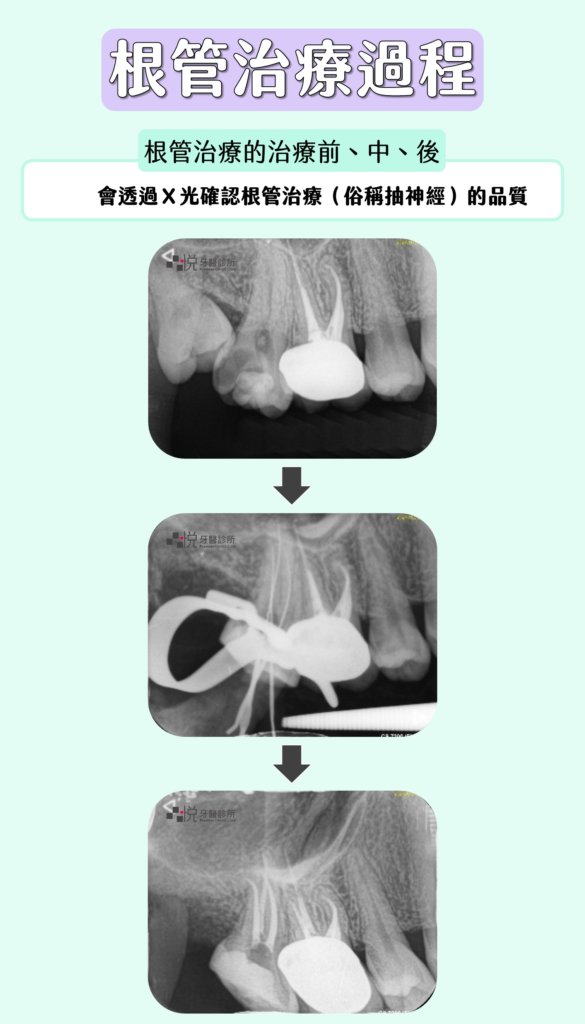

根管治療(抽神經)過程

在根管治療(俗稱抽神經)的治療前、中、後,會透過拍攝X光片,以確認根管治療的品質

以X光確認根管治療品質。